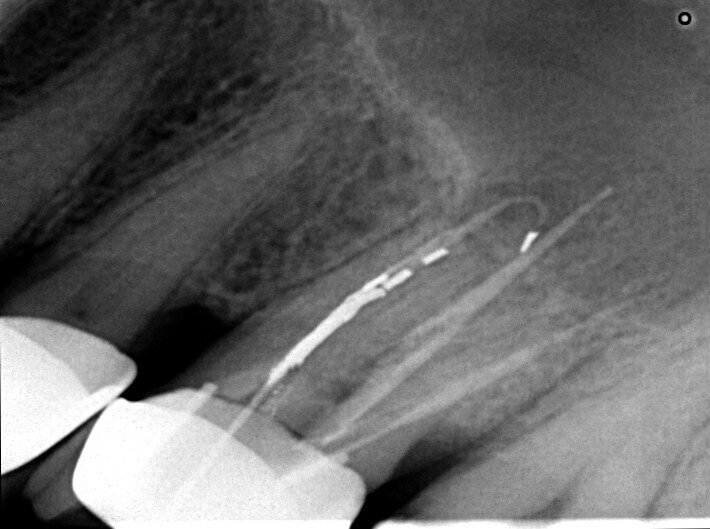

A patient was referred to the office with problems related to separated files. He was a pilot and was complaining of pus draining from his nose when flying. From the preoperative radiograph (Fig. 1), it was clear that there were two separated file fragments in the mesial canals and one cone passing beyond the apex in the palatal root. I requested an iCAT scan, and from this, the left sinus was clearly almost full with inflammatory fluid (Fig. 2) and the cone in the palatal canal was clearly emerging into the sinus. We could also see the two separated files in the two mesial canals clearly in the MPR view (Figs. 3 & 4), as well as another file entering the sinus and not attached to the canal (Fig. 5). We could see the file using different filters (Figs. 6–9), as well as the inflammation inside the sinus and the separated file. We additionally gained a better idea of the location of the cone protruding from the palatal canal into the sinus.

The treatment plan was to try to solve it with a conventional approach and if necessary to perform microsurgery to save the tooth. With the help of H-files, I managed to retrieve the cone from the palatal root, but the files inside the mesial root were impossible to bypass or even to reach with ultrasonic tips. I decided not to overdo it in order to avoid creating an additional problem, like perforating the canal, and decided to seal the canals (Fig. 10). A surgical approach was immediately taken for the mesial canals, cutting 3 mm of the mesial root using the Impact Air handpiece (SybronEndo), and this gave me a direct view of the Schneiderian membrane, where the third file was barely hanging (Figs. 11 & 12). I managed to delicate grab it and to remove it (Fig. 13). Figure 14 shows the postoperative situation, after performing retrograde preparation of the mesial canals.